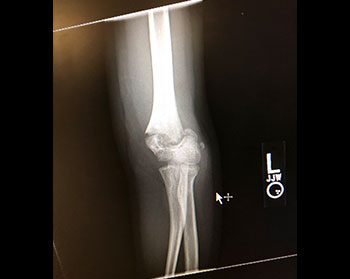

This clinical practice guideline addresses the treatment of isolated supracondylar fractures of the humerus in children who have not yet reached skeletal maturity.

Photo Courtesy of Matthew R. Schmitz, MD, FAAOS